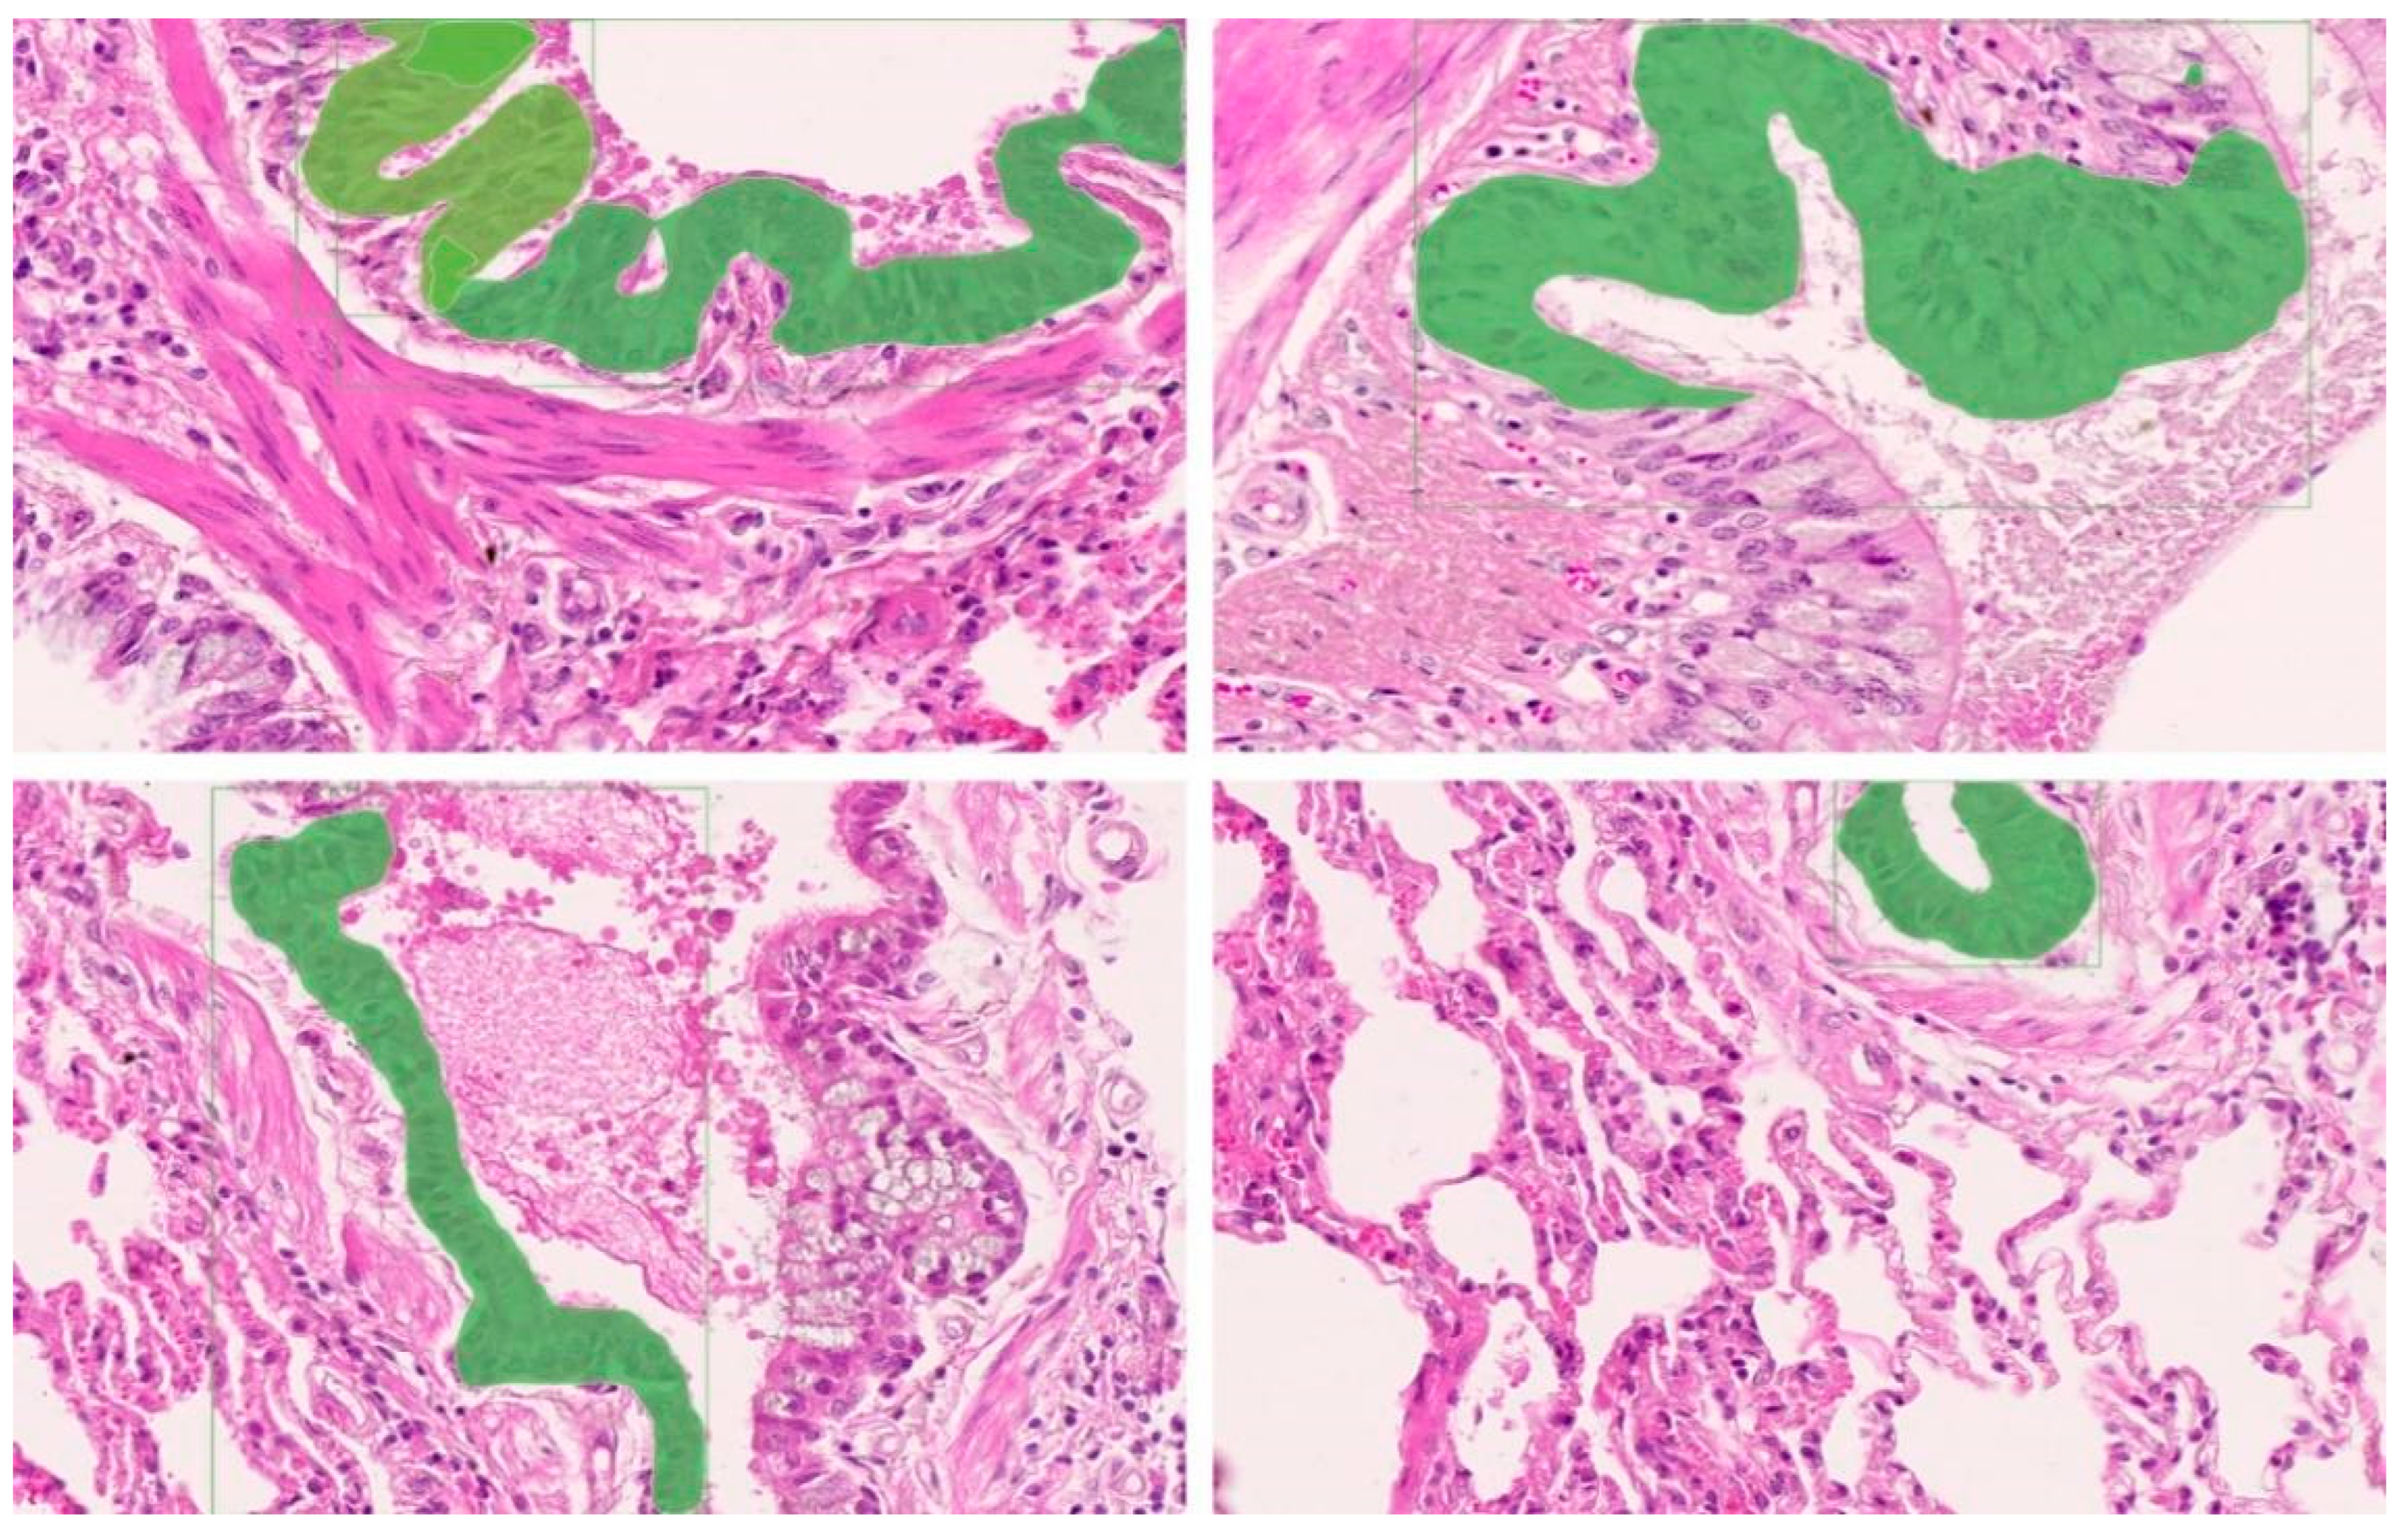

2.3. Establishment of the Training Dataset for the Mask R-CNN OPA Pathological Diagnostic Model

3.3. Mask R-CNN OPA Pathological Diagnostic Model Anti-Peeking Verification Results